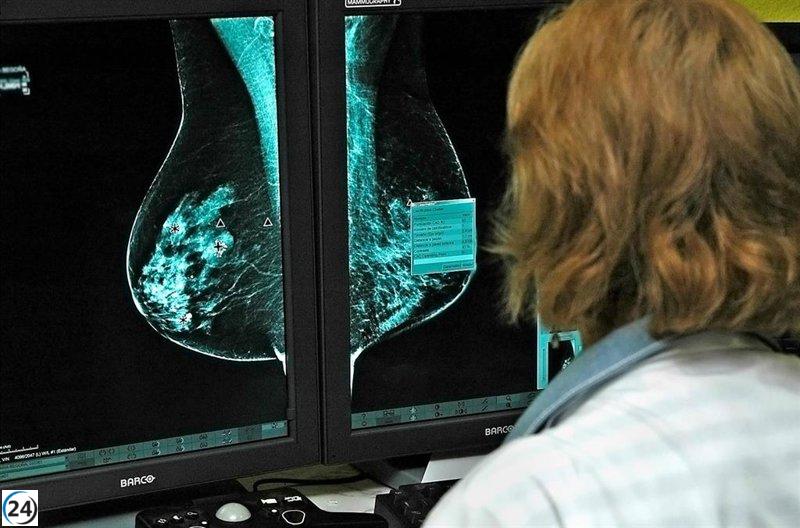

La Sociedad Andaluza de Oncología Médica (SAOM) ha expresado su apoyo al plan de acción propuesto por la Consejería de Salud y Consumo, destinado a mejorar el programa de detección temprana de cáncer de mama en Andalucía. Este nuevo enfoque surge a raíz de fallos en la comunicación de resultados y en la gestión de citas en varios hospitales de la región.

Corral ha aclarado que el cribado mamográfico es un pilar esencial en la salud pública que debe apoyarse en protocolos uniformes, recursos adecuados y personal cualificado. La sociedad también destaca su compromiso con la investigación y la mejora constante de la oncología mamaria en Andalucía.